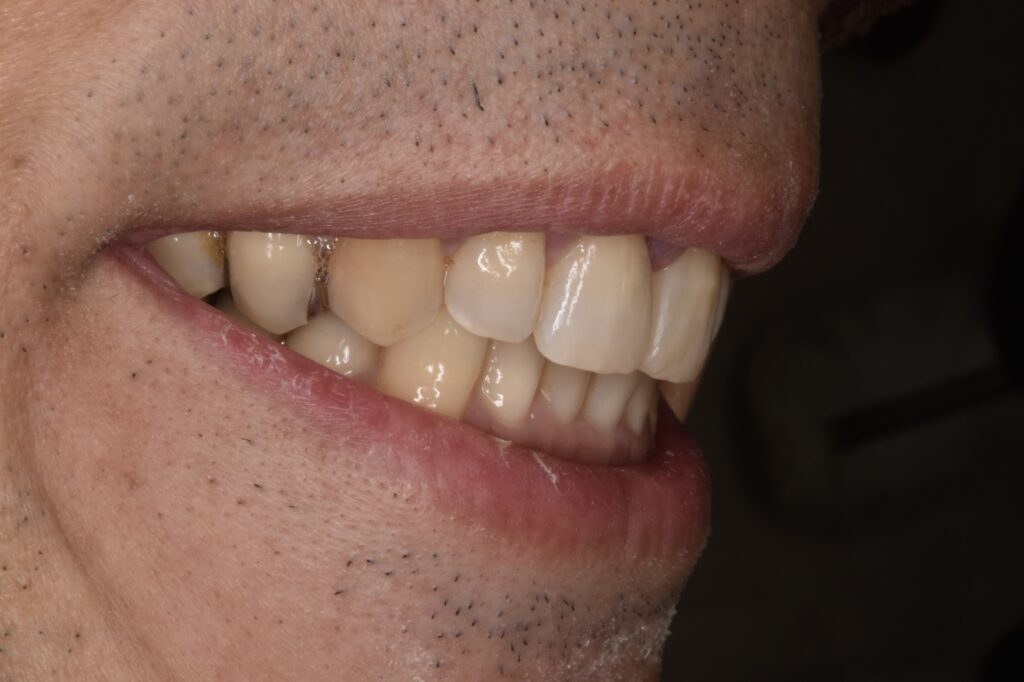

50代男性です。当院にご相談してくださる前に他院で前歯2本のダイレクトボンディング?を受けられたそうです。前歯2本の隙間は確かに白いレジンで埋められていましたが、本当に盛って作っただけのもので、違和感がかなり強かったそうです。

当院でタイレクトボンディング2歯のやりかえをご希望されて、2本でご契約してくださいました。他院のレジンは前日に取れたそうです。

治療後

約2時間後です。

治療前とは比べ物にならないほど自然だと大変喜んでくだいました。歯のもっこり感もなくちゃんとフロスも通ります。